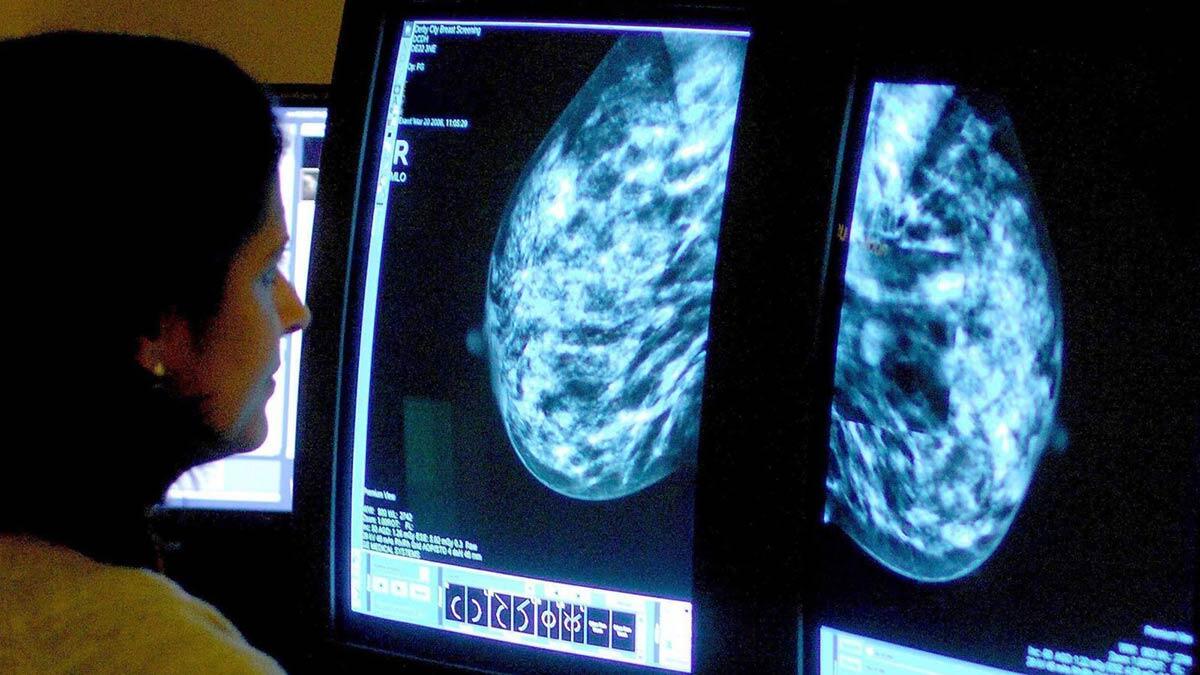

İngiltere’de meme kanserine karşı tedavide yeni uygulanan Phesgo’nun kullanımına onay çıktı. İngiltere Ulusal Sağlık Kurumu (NHS) tarafından onaylanan tedavi yönteminin sağlık çalışanlarına daha fazla zaman kazandırdığı kaydedildi.

‘Şimdi Göğüs Kanseri’ adlı yardım kuruluşunun CEO’su Barones Delyth Morgan basına yaptığı açıklamada, Phesgo’nun NHS onayını ‘harika bir haber’ olarak nitelendirdi. Morgan, binlerce kadının ‘daha hızlı ve daha nazik” bir tedavi yönteminden yararlanacağını söyledi. Phesgo’nun, kemoterapi ile birlikte HER2 pozitif meme kanserinin tüm aşamalarını tedavi etmek için kullanılacağı belirtildi.